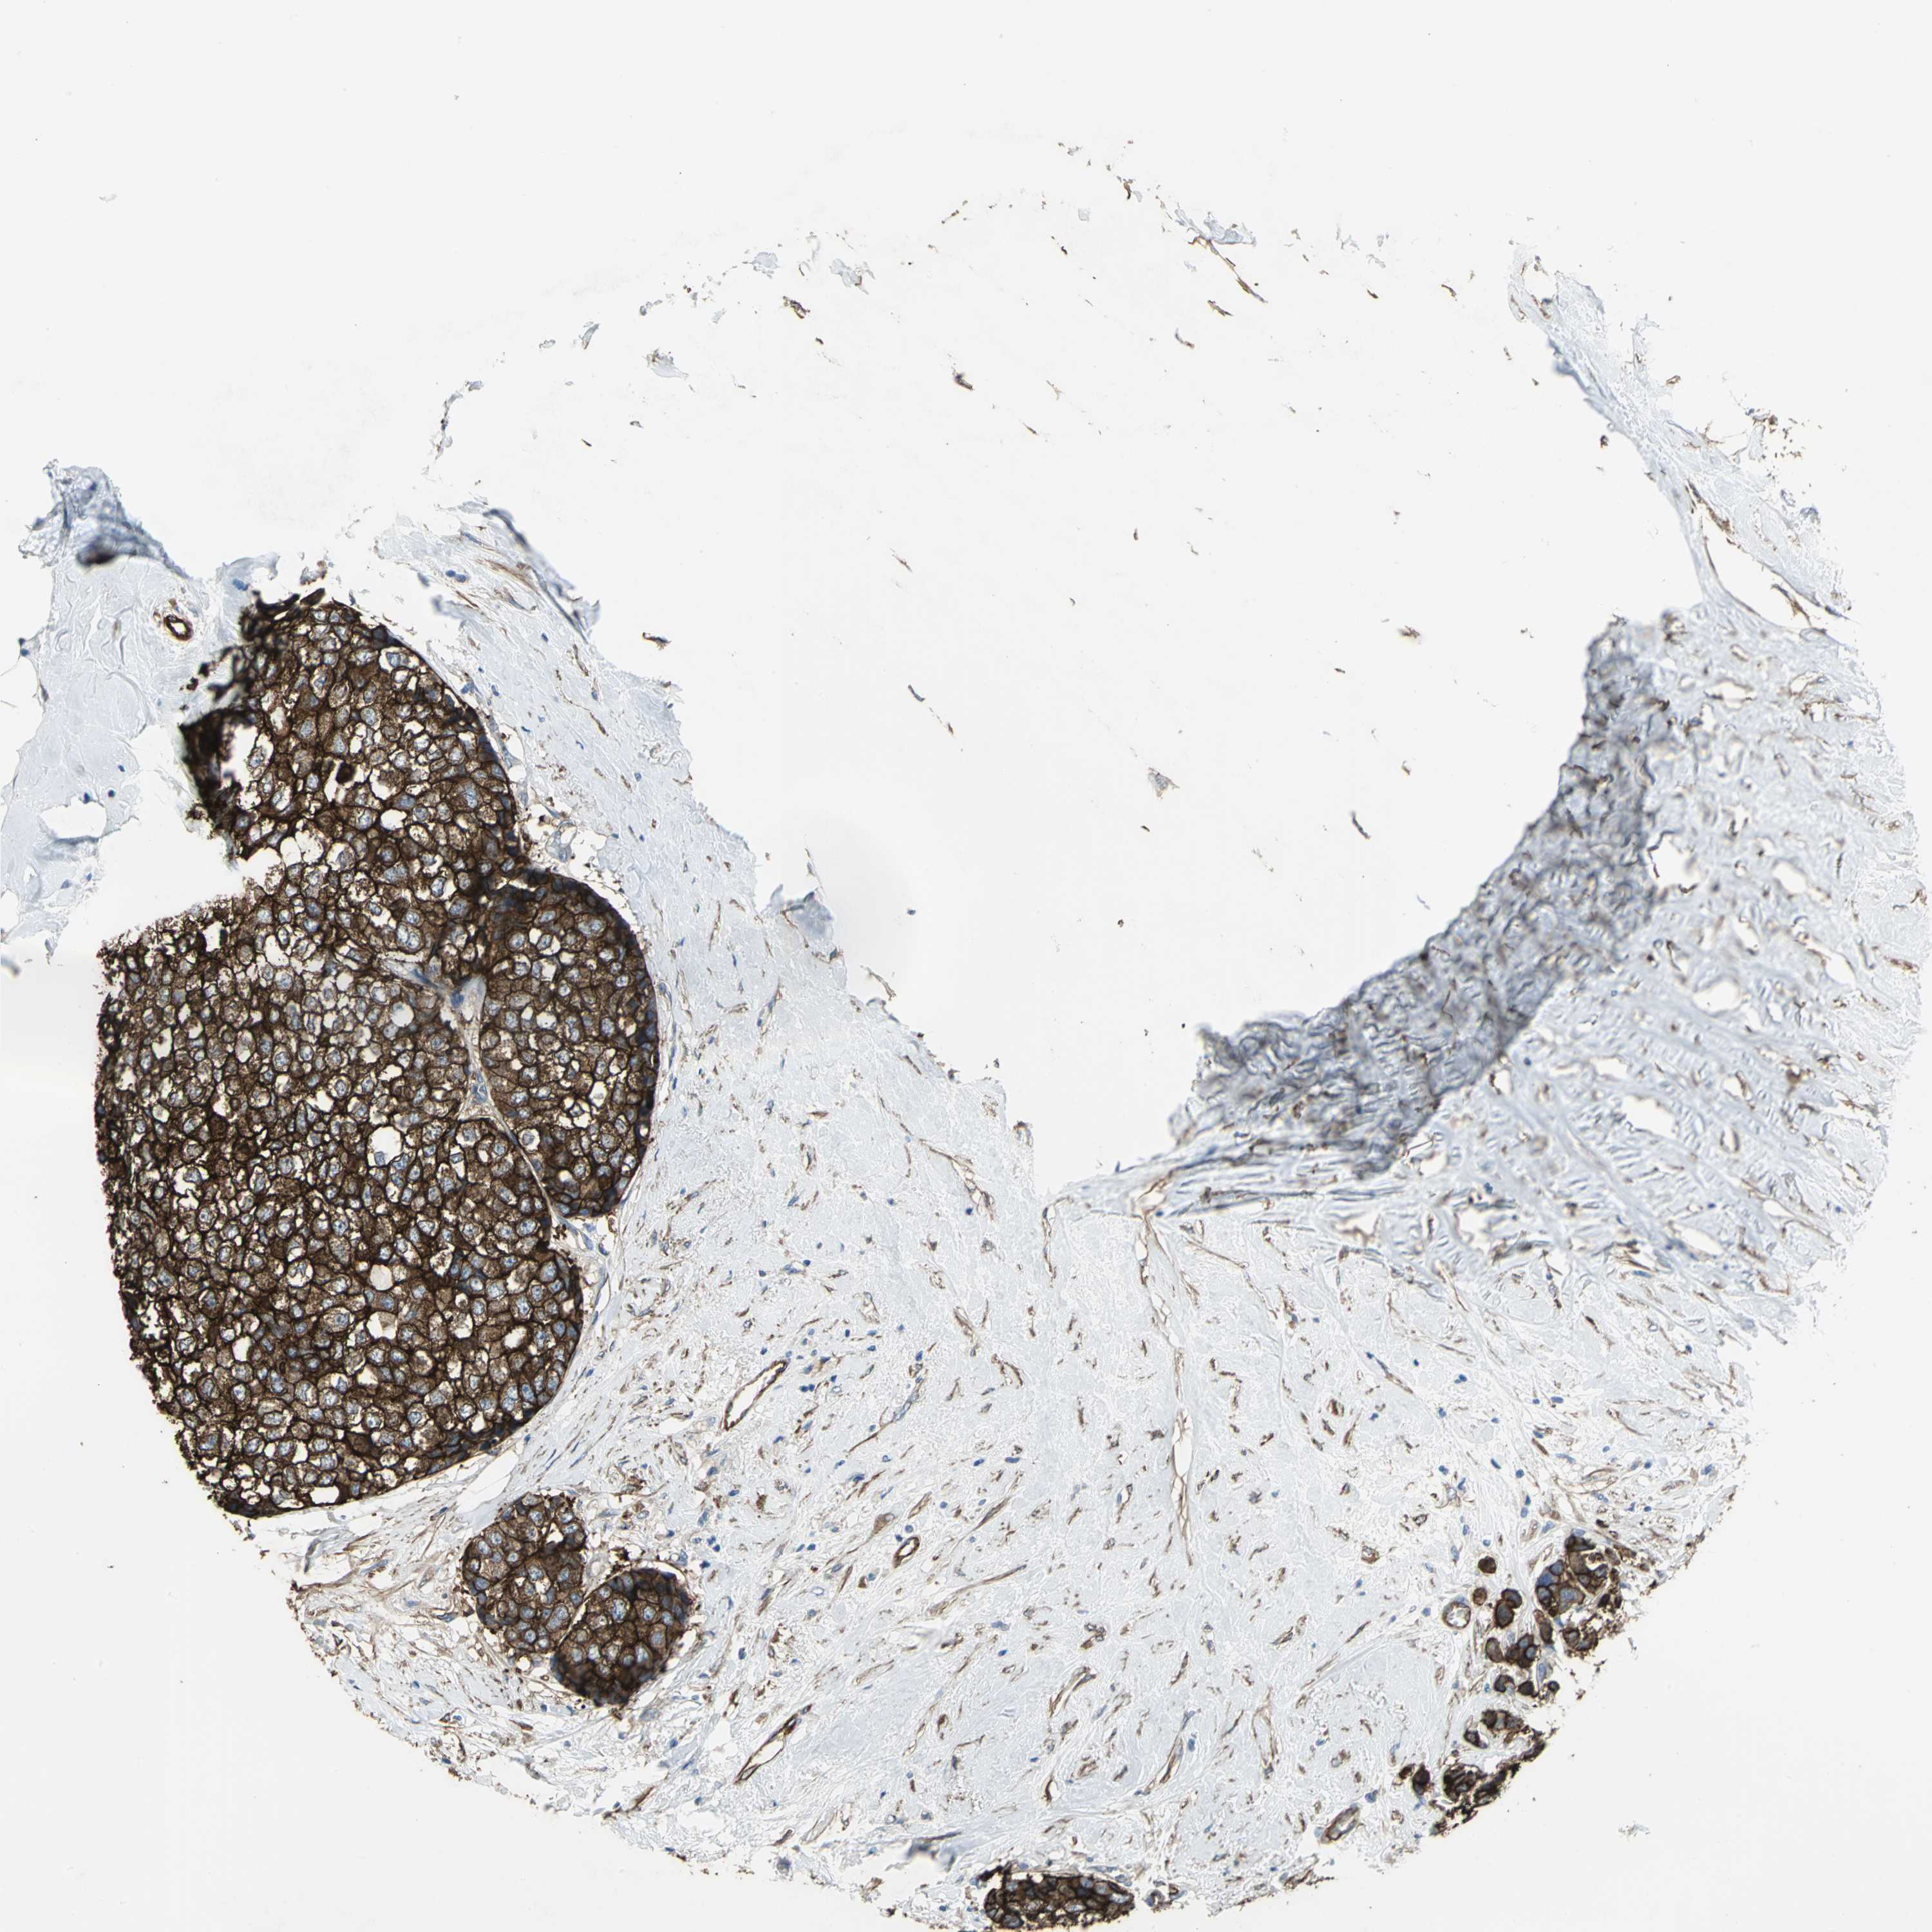

CANCER BREAST CANCER Show tissue menu

BRCA TCGA BRCA VALIDATION PROTEIN EXPRESSION

ANTIBODIES

AND

VALIDATION